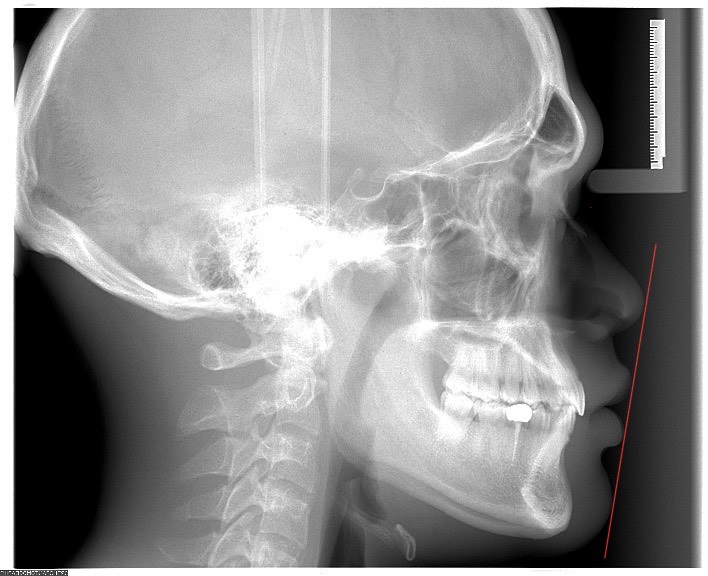

To reduce bimaxillary protrusion, one treatment ik is Premolar Extraction + Braces.

To reduce bimaxillary protrusion, one treatment ik is Premolar Extraction + Braces.

- Am I a good candidate for this surgery?